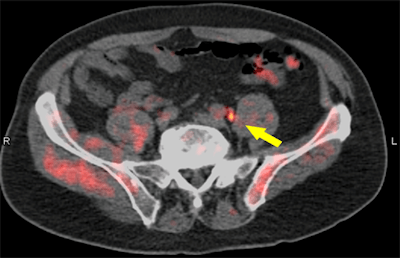

The LOCATE trial measured the percentage of men with suspected biochemical recurrence of prostate cancer following initial prior therapy whose treatment plan changed after PET/CT scans with fluciclovine (Axumin, Blue Earth Diagnostics). Researchers also focused on the association between positive scan results and the clinical recurrence of the cancer, as well as prostate-specific antigen (PSA) levels and Gleason scores.

The researchers found that 126 patients (59%) had their clinical management changed due to the fluciclovine-PET results. Among those changes, 98 men (78%) had major alterations in treatment strategy, including a change in modality. In addition, disease was detected in the prostate, pelvic tissue, abdominal lymph nodes, and, less commonly, bone. Interestingly, fluciclovine-PET influenced the treatment management of 36 (39%) of 91 men with negative scan results. In addition, there was no association between Gleason scores at diagnosis and positive scans.